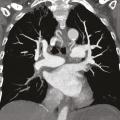

Dans le cas de monsieur M., l’embolie pulmonaire étant probable (en raison de l’antécédent de thrombose veineuse profonde et de la tachycardie à 115 batt/min), l’angio-TDM thoracique est réalisée d’emblée et confirme le diagnostic d’embolie pulmonaire proximale bilatérale (fig. 2) avec dilatation des cavités cardiaques droites et reflux dans la veine cave inférieure.

La prise en charge de l’hyper- tension pulmonaire thrombo- embolique chronique dépend de la localisation des séquelles thromboemboliques, proximale ou distale. Deux examens sont utiles à ce stade, l’angio-TDM thoracique (fig. 6) et l’angiographie pulmonaire (fig. 7).